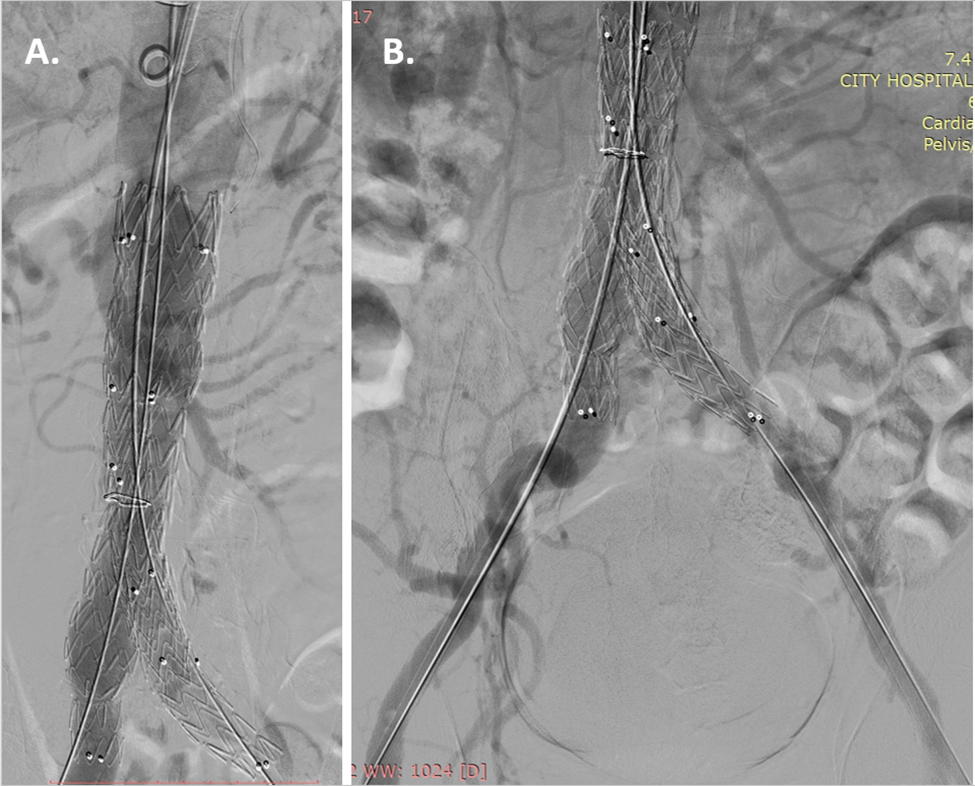

Fig. 3.Stent-graft implantation. (A) Stent- graft Endurant II 36/16/145 mm (Medtronic, MN, USA) implantation in the abdominal aorta and (B) extension into the two iliac arteries Endurant II 16/20/124 mm (Medtronic, MN, USA) into the right iliac artery and Endurant II 16/16/82 mm (Medtronic, MN, USA) into the left iliac artery, were implanted.